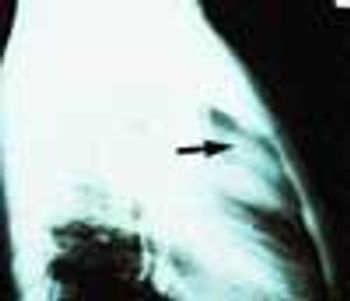

Police brought a delirious, combative 24-year-old man to the emergency department. The patient was unable to provide any history on arrival, but his scarred, blistering lips and his vital signs (blood pressure, 166/102 mm Hg; heart rate, 97 beats per minute; respiratory rate, 24 breaths per minute; and temperature, 38.2°C, or 100.9°F) led to a possible diagnosis of cocaine-induced delirium.